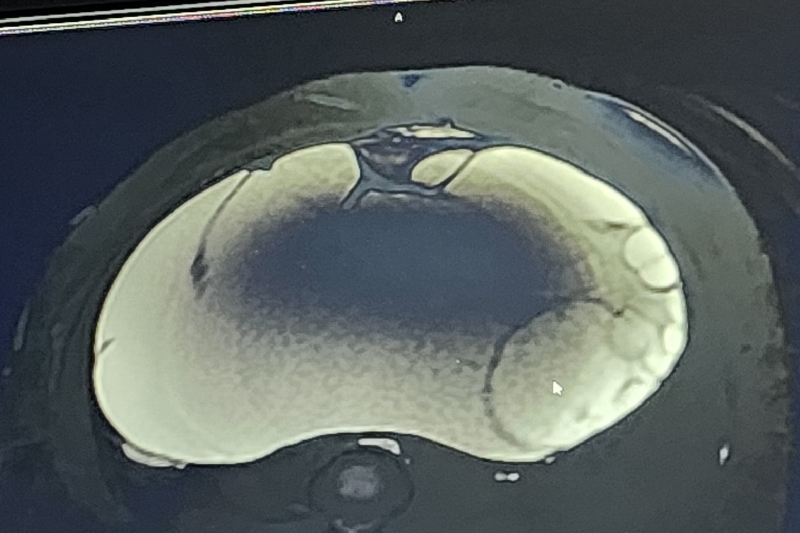

My daughter, Francesca, 37 a single mother of one has been diagnosed with a enormous ovarian cyst that has a high possibly of malignancy. She must undergo surgery to remove the 13 inch by 11 inch mass that will put her out of work for six to eight weeks if the surgery goes as planned. It will take several more weeks for her to get back on her feet due to the size of the mass. She is a wonderful young lady whose passion, when not working to support her child, is to spend time with her seven year old son at the park. She actively assist me with the daily activities of my 92 year old mother suffering from extreme dementia.